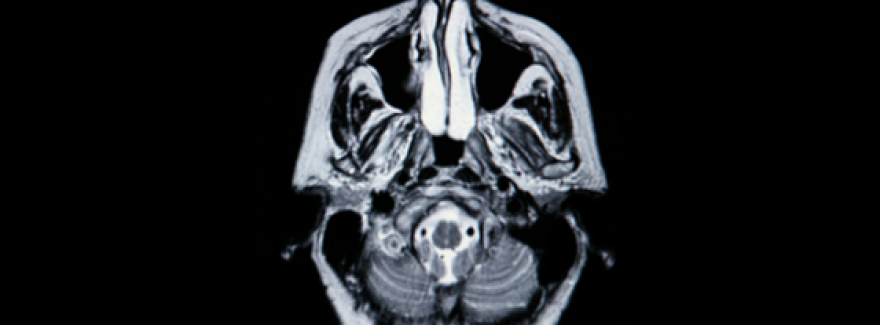

In an original published research paper from 2014 called Reduction in Arterial Blood Pressure Following Adjustment of Atlas to Correct Vertebral Subluxation: A Prospective Longitudinal Cohort Study, authors discussed the correction of what we call The Atlas Displacement Complex.

This is just more evidence that upper cervical displacement, a shift in the position of the upper cervical spine (CORE PROBLEM) can affect the spinal cord and nervous system in ways that alter the regulation of blood pressure (COLLATERAL DAMAGE).